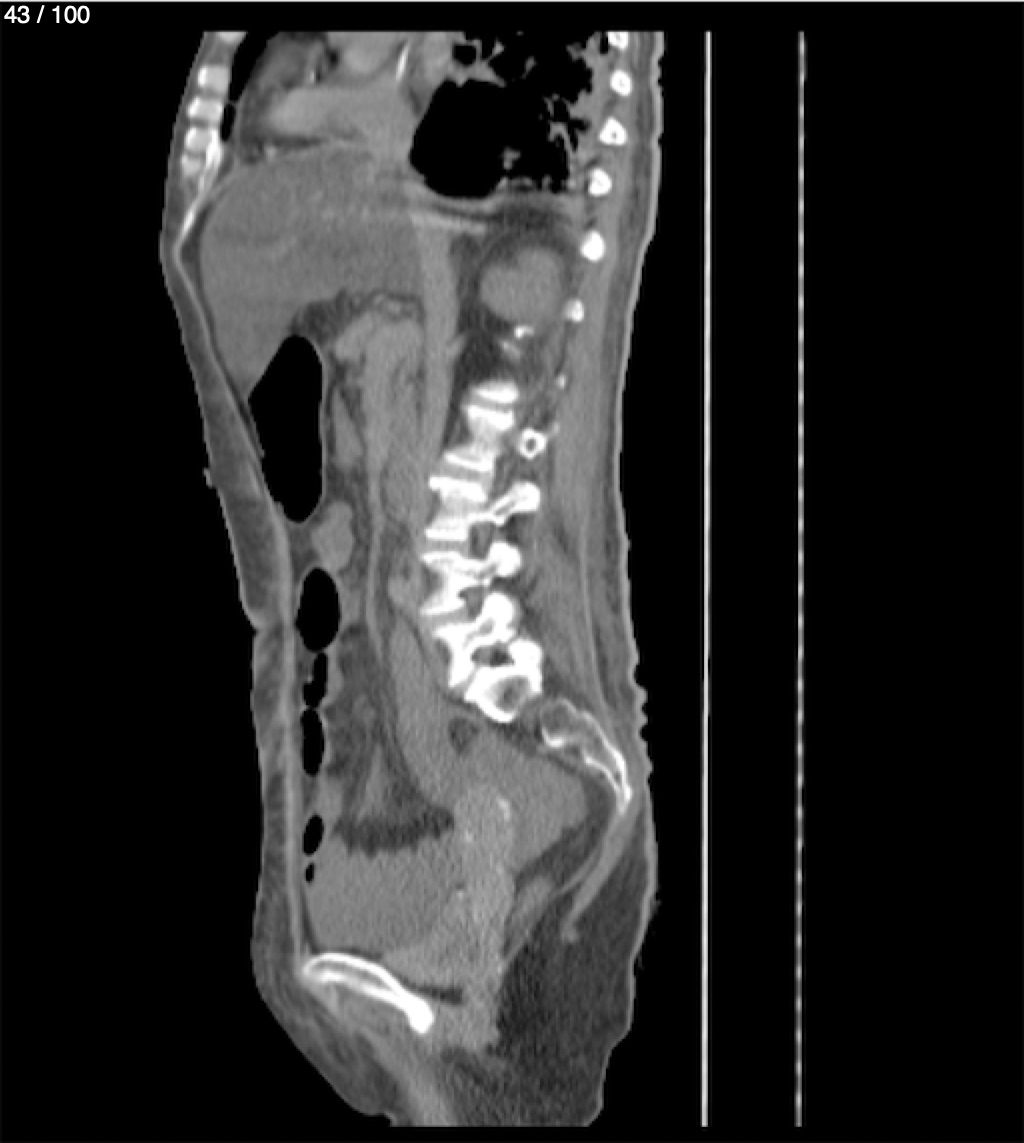

Hilda Geronimo Mendez 60A - T.C Abdomen Simple